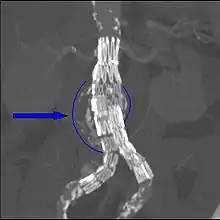

Abdominal aortic endograft on a CT scan; original aneurysm marked in blue